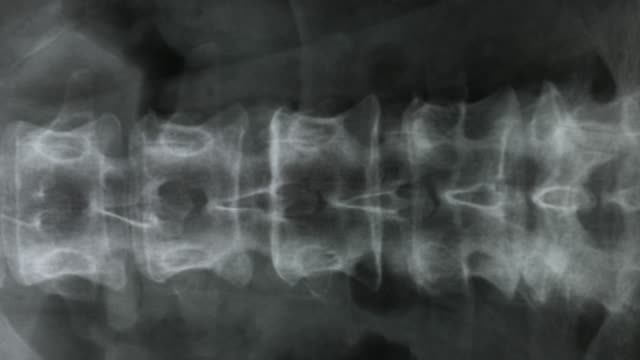

척추관협착증은 척추 주변의 근육과 인대가 퇴행하여 척추관 내 황색 인대가 비정상적으로 부풀어 오르면서 발생하는 퇴행성 척추질환 중 하나입니다. 이 질환은 가까운 거리도 통증으로 인해 걷기가 어려워지는 특징을 가지고 있으며, 새벽에 다리에 통증을 느끼는 경우가 많습니다.

척추관협착증은 다른 척추 질환에 비해 퇴계 정도가 매우 심한 질환으로, 퇴행이 심할수록 근육과 인대가 더욱 뭉쳐지고 더 많은 압력을 가하게 됩니다. 이 때문에 근육과 인대를 풀어주는 것이 중요하며, 이를 위한 가장 적합한 운동이 걷기입니다.